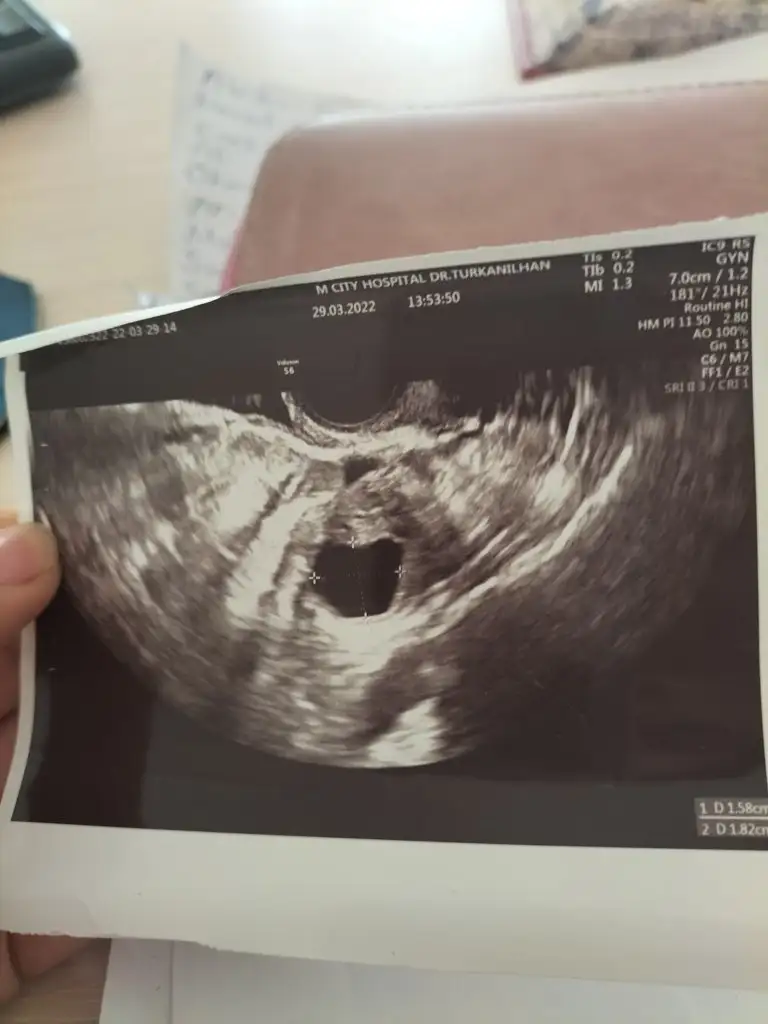

Bir gebenin günlüğü diye bi YouTube sayfası var orada yumurtlama nasajı var onu yap canım sol yumurtalığına inşallah faydasını görürsünHerkese Merhaba; öncelikle hamile olan arkadaşlarımı tebrik ederim, kısaca başımdan geçenleri size anlatmak istiyorum ben şubat ayında dış gebelik ameliyatı oldum ve sağ tüpüm alındı ama aynı zamanda sol yumurtalığımdaki kistimi de almışlar, uyandığımda öğrendim....

Doktor koruma süresini 2 adet süresi demişti 2.adetimde 1 nisan itibari ile bitti yani denemelere başlayabilirim bat 25 nisan

beni de ekleyebilir misiniz? ovulasyonla yumurtlamayı takip edeceğim ama tabi hamile kalabiilmem için sol dan yumurtlamam gerekiyor bakalım Allah nasip ederse olur...

Evet normal de benim yumurtlama 1 Nisan da görünüyordu 29 unda muayeneye gittim doktor bugün yumurtan ya çatladı ya da çatlayacak demişti zaten akşamına ovulasyon testim silikleşti 2 gündür de adet belirtilerim başladı benim 10 gün önceden başlarYa ahahahahaha şaka gibi resmen

Kaç mm di canım yumurtan ay hayırlısı olsun ikimiz içinde bu ayEvet normal de benim yumurtlama 1 Nisan da görünüyordu 29 unda muayeneye gittim doktor bugün yumurtan ya çatladı ya da çatlayacak demişti zaten akşamına ovulasyon testim silikleşti 2 gündür de adet belirtilerim başladı benim 10 gün önceden başlar